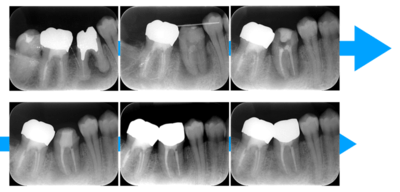

2021.4.3 定期検診時

この時はまだ症状がなかった

しかし歯は縦に割れており、いつ痛みが出てもおかしくないような状態であることは説明していた。

2022.1.15 根尖性歯周炎の急性化

疼痛ありで急患来院。

前々から爆弾抱えているような物で、何かあったら抜歯と伝えていた部位。以前よりクラウンマージン下で歯根縦破折であったが、症状なしで経過観察をおこなっていた。

抜歯予定とし、アモキシシリンとロキソニンを処方した。

2022.2.5 抜歯後の消毒

口腔内写真

CT画像

骨の状態はそこまで悪くないが、欠損が大きい。

2022.3.12 抜歯1ヶ月後・移植

移植オペ

抜歯をして1ヶ月後、歯ぐきが治ってから、移植をおこなった。

移植時は動揺が大きいため、隣の歯にワイヤーで固定した。

2022.4.16 根管充填

移植2週間後から根管治療開始

次の回(翌週)で根管充填

2022.5 仮歯装着

根管治療後は仮歯をいれて経過をみていきました。

日に日に動揺がなくなっていくのがわかりました。

2022.7.9 経過観察後

レントゲン写真

根管治療後3ヶ月です。根のまわりの骨がやや白くなってきているのがわかります。だんだん骨の添加がみられている証拠になります。

ここまで治癒していればかぶせ物をかぶせても問題ないと判断しました。

2022.8.13 クラウンセット

2022.10.16 予後経過

1年後 2023.3 予後経過

移植した歯はしっかり機能しており、問題なく使用できているとのことである。

最後のレントゲンでは、骨がしっかり添加され、周囲組織となんら変色ない状態にまでなっていることがわかる。